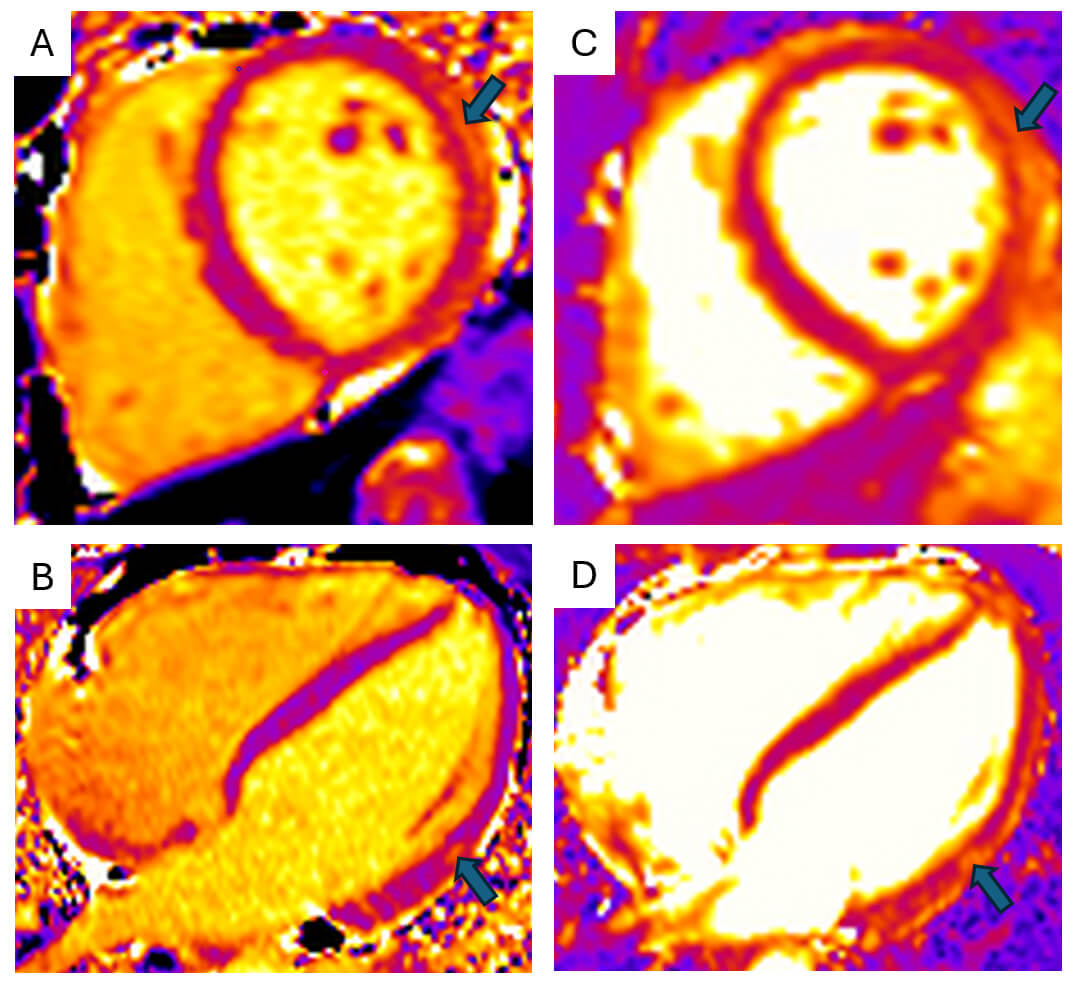

Contemporary methods, such as strain analysis (Fig. 1), which measure the displacement of tissue (pixels) and thus strain over the course of the cardiac cycle, can be helpful in cases of myocarditis owing to the inability of echocardiography to accurately characterise myocardial inflammation. Global longitudinal and radial strain correspond to areas of myocardial inflammation on biopsy [20] and, in both 2D and 3D imaging, have been correlated with regional changes of inflammation and late gadolinium enhancement (LGE) on CMR [21, 22].

Fig. 1.

Echocardiogram with endocardial speckle tracking and global longitudinal strain analysis. (A) 2D apical 4-chamber view with endocardial border speckle-tracking. (B) Upper: EndoGLS over time (ms), and lower: LV volume curve (red) and dV/dt (blue) over time (ms). (C) Reference plot for global longitudinal strain (GLS) vs LVEF. (D) 16-segment polar map if segmental EndoGLS demonstrating regional reduction in longitudinal strain, particularly affecting the basal inferior and inferolateral segments. ES, End-Systole; TTP, Time to Peak; EndoGLS, endocardial global longitudinal strain; EF, ejection fraction; EDV, End-Diastolic Volume; ESV, End-Systolic Volume; ESL, End-Systolic Length; ESDbas, End-Systolic Diameter, basal; EDL, End-Diastolic Length; EDDbas, End-Diastolic Diameter, basal; SD-LS-Syst., Standard Deviation of Longitudinal Strain during Systole.